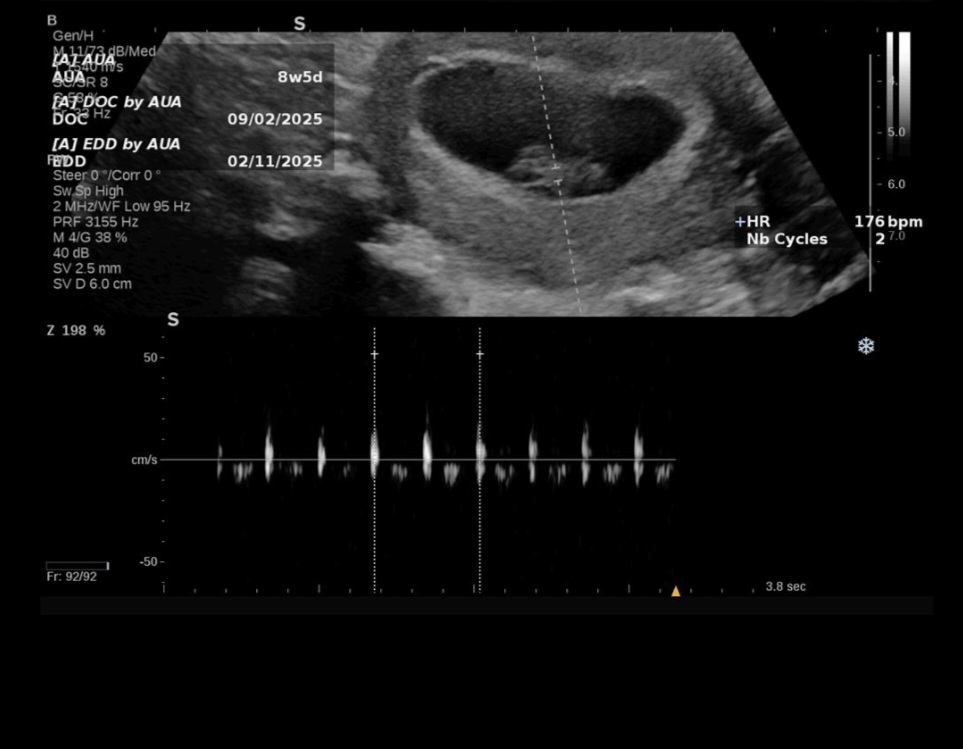

فک کنم پسر این عکس چند هفتس

۱۲ هفته از روی مانیتور سونو عکس رو گرفتم